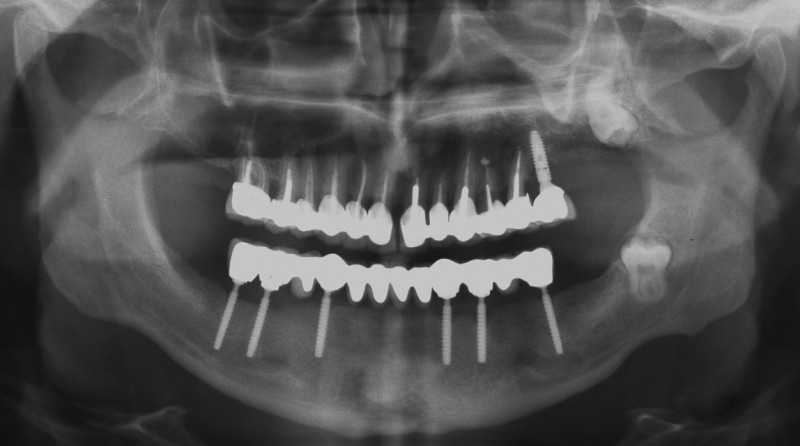

Рентгенова снимка през 2025 година – лека резорбция на костта, нормална за 15 години функционален престой на имплантатите с моста. Пациентът няма оплаквания и се храни нормално.

![/userfiles/files/04-cortico-basal-implants.jpg [/userfiles/files/04-cortico-basal-implants.jpg]](/userfiles/files/04-cortico-basal-implants.jpg)

Пациентът има горна тотална плакова протеза, която лепи с Корега и така се чувства сравнително комфортно. Ето защо започнах лечението от долната челюст. Предстои лечение на горната по същия начин.